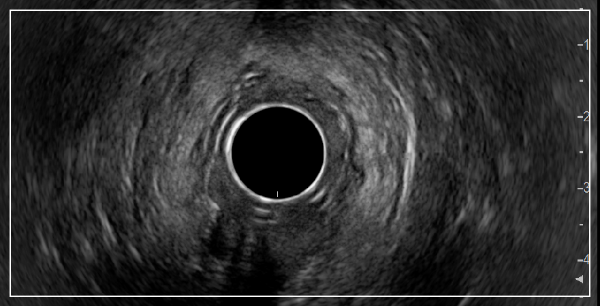

최신형 항문 초음파 도입으로 덜 아프고 정확하게 초음파 진단이 가능합니다.